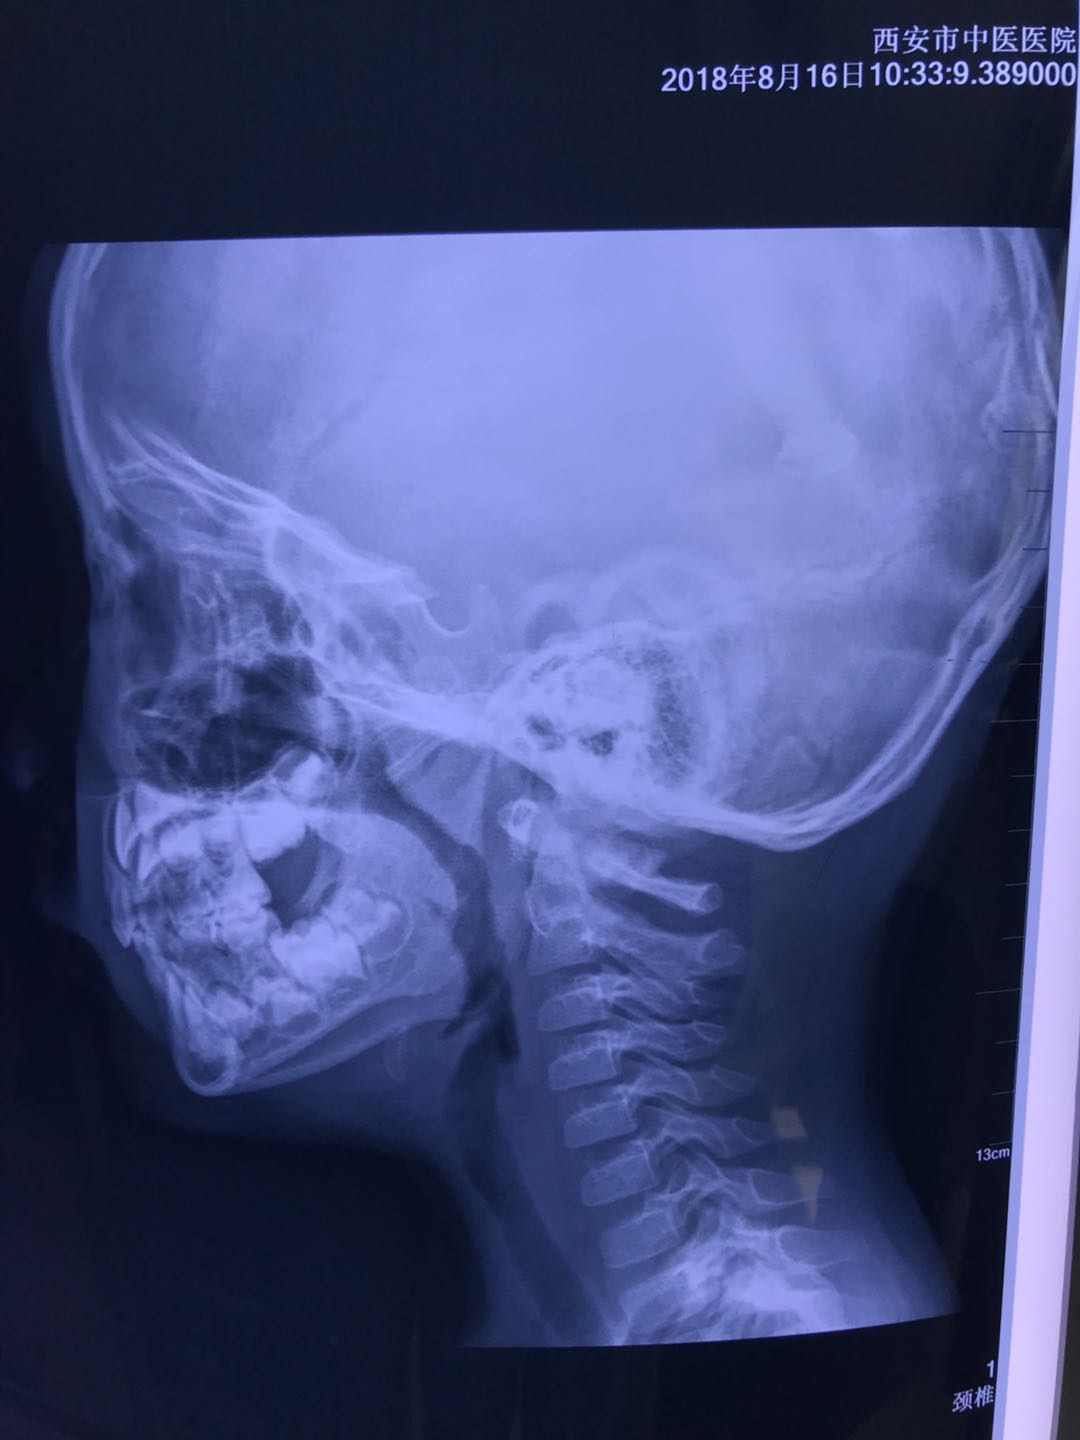

注:因患儿在当地鼻咽侧位片未标明A/N比值,故本次行鼻咽侧位片检查,A/N比值示0.85。

2018年8月16日 三诊,患儿无打鼾,无张口呼吸,无鼻塞及流涕,无咳嗽,查体:咽稍充血,双侧扁桃体I°肿大,心肺腹无异常,舌质淡,苔薄白,脉沉。

注:复查鼻咽侧位片示A/N比值示0.7。